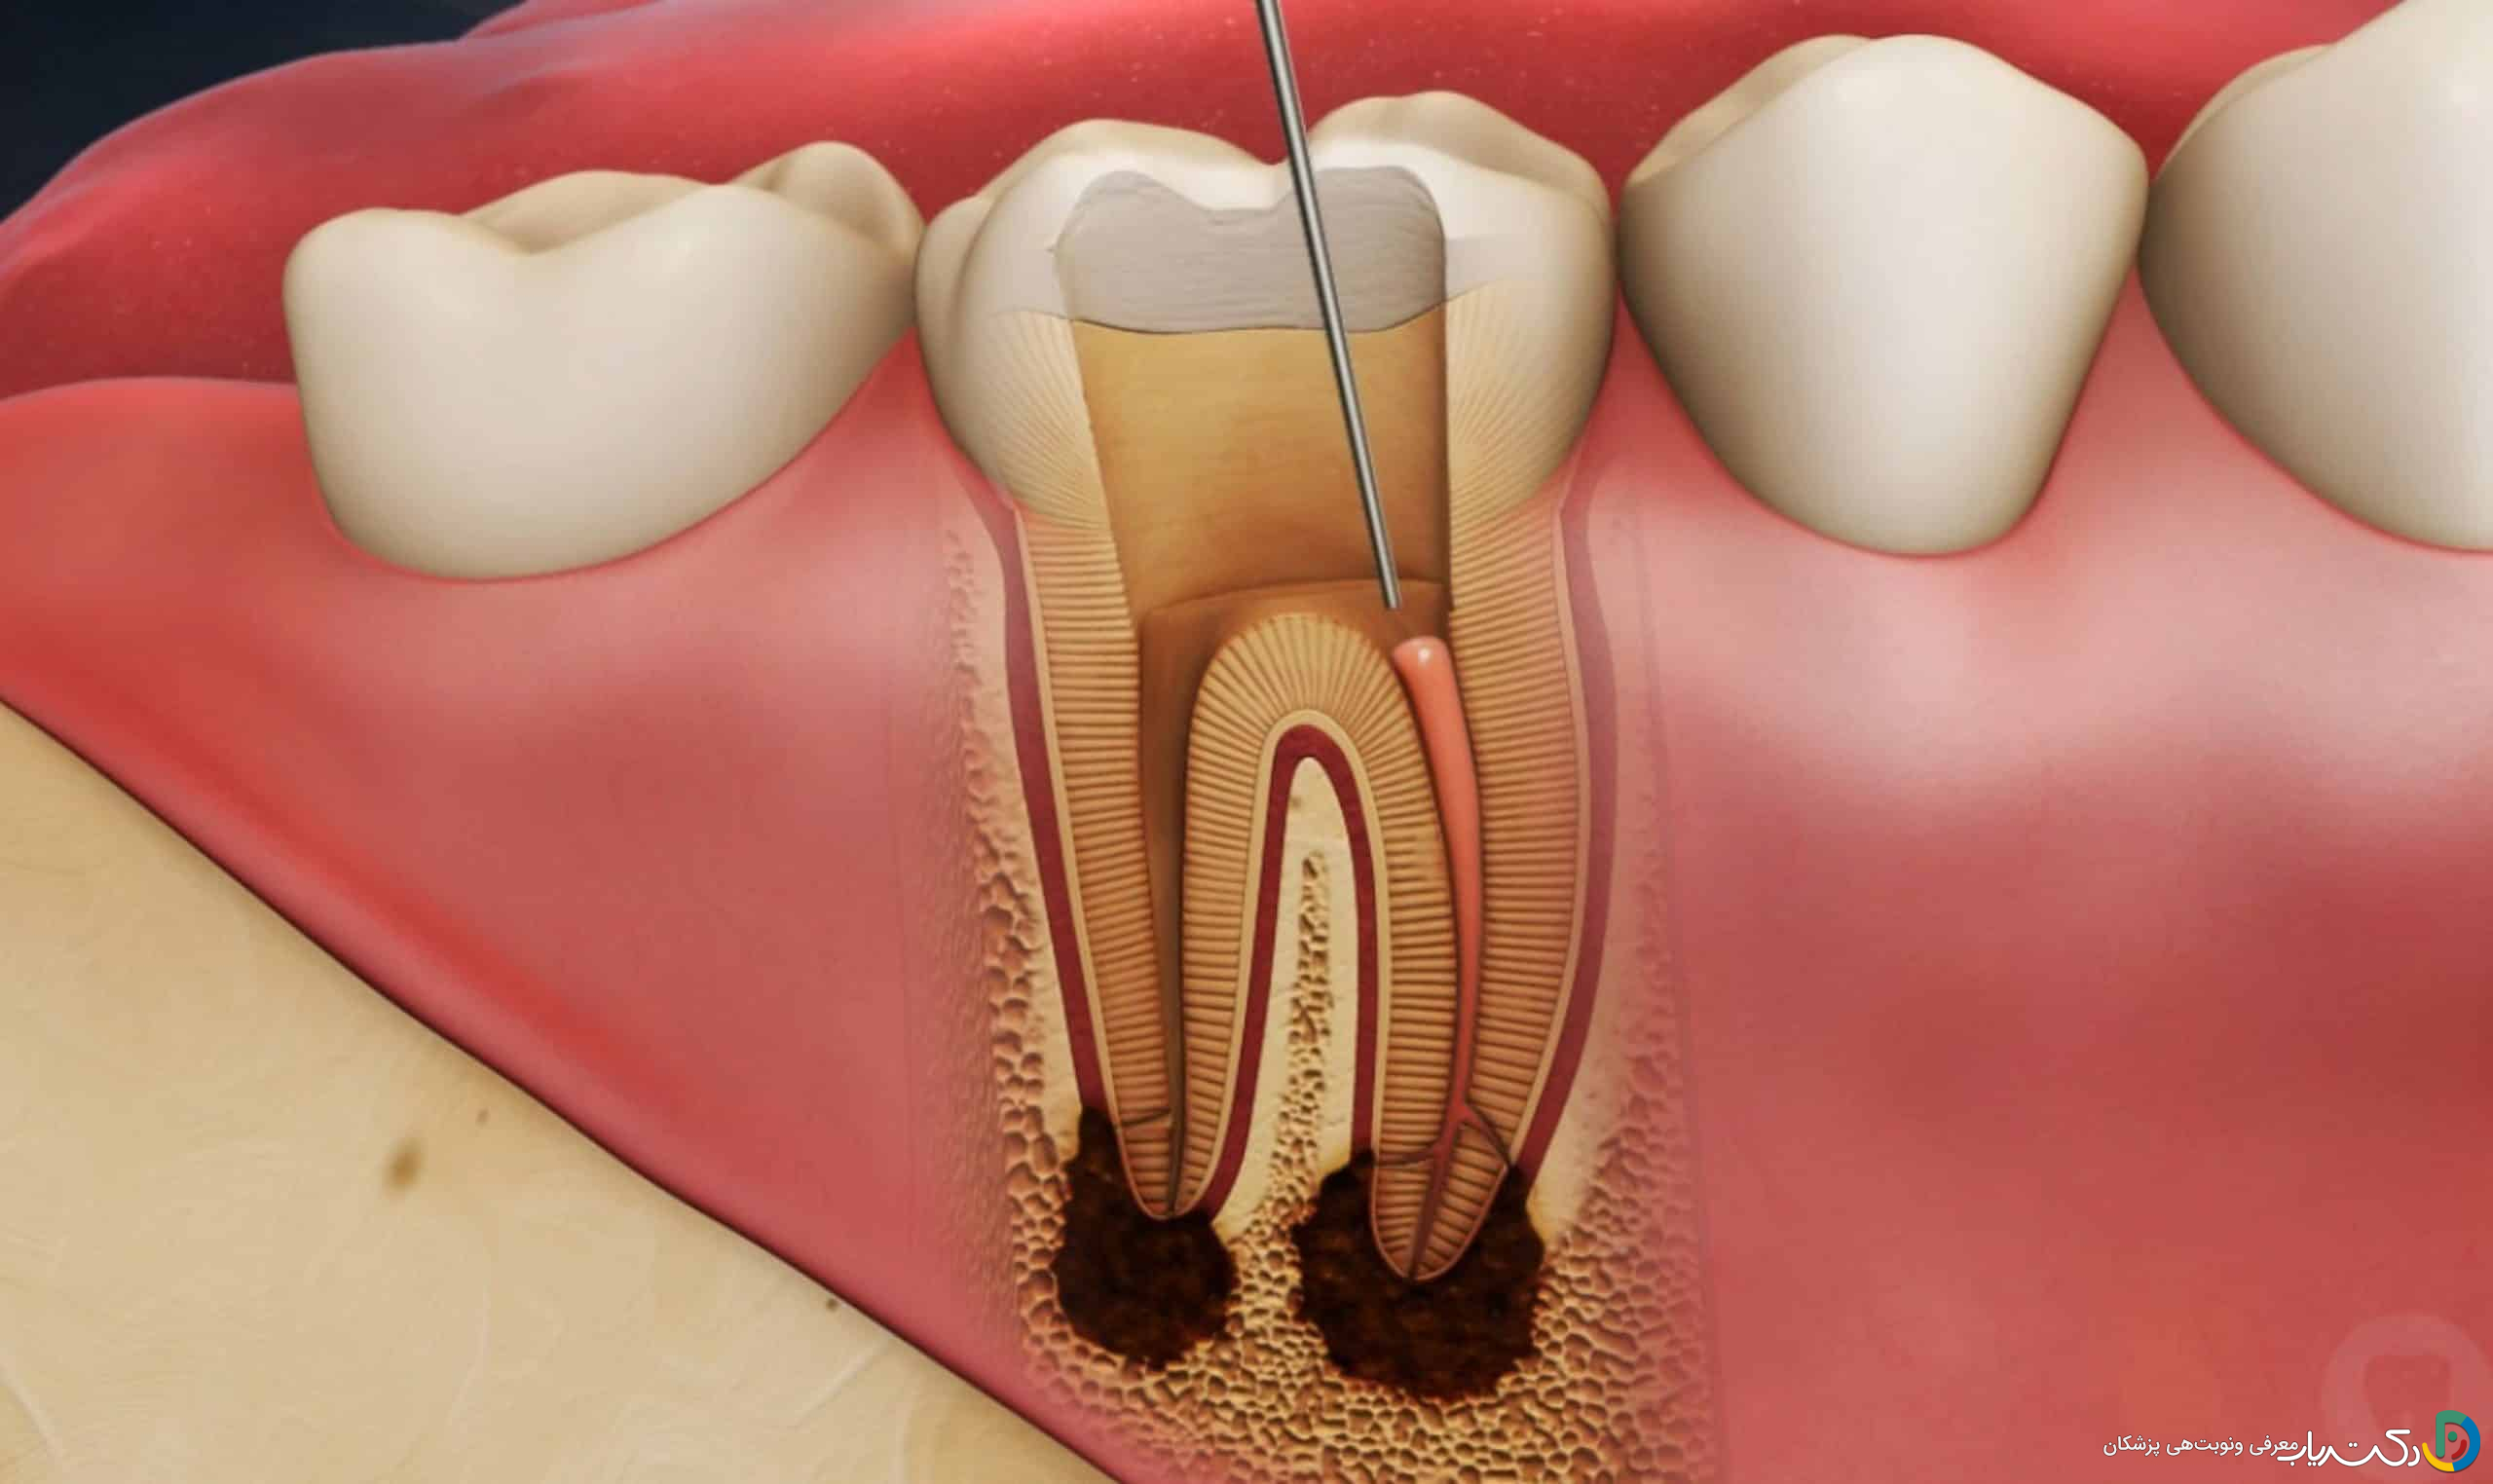

عصبکشی دندان (درمان ریشه یا اندودانتیکس) یک روش درمانی بسیار موفق و ضروری برای نجات دندانهایی است که پالپ (عصب و عروق خونی) آنها دچار عفونت یا التهاب غیرقابلبرگشت شده است. این درمان از کشیدن دندان جلوگیری کرده و به حفظ ساختار طبیعی دهان کمک میکند. با این حال، مانند هر مداخله پزشکی دیگری، عصبکشی نیز میتواند با مجموعهای از عوارض جانبی همراه باشد. خوشبختانه، اکثر این عوارض خفیف، موقتی و قابل کنترل هستند و با انتخاب یک دندانپزشک ماهر و رعایت دقیق مراقبتهای پس از درمان، میتوان احتمال وقوع آنها را به حداقل رساند.

علت: پس از درمان، بافتهای اطراف ریشه دندان (لیگامان پریودنتال) به دلیل استفاده از ابزارهای دندانپزشکی و پاکسازی کانالها، دچار التهاب جزئی میشوند. این التهاب طبیعی است و باعث ایجاد درد خفیف تا متوسط، بهویژه هنگام جویدن یا فشار آوردن روی دندان، میشود. تورم خفیف در لثه اطراف دندان نیز ممکن است مشاهده شود. مدیریت: این درد معمولاً با مسکنهای بدون نسخه مانند ایبوپروفن یا استامینوفن بهخوبی کنترل میشود و طی چند روز بهتدریج کاهش مییابد.

- کانالهای فرعی یا پنهان: برخی دندانها دارای آناتومی پیچیدهای هستند و ممکن است یک کانال بسیار باریک یا فرعی از دید دندانپزشک پنهان بماند و پاکسازی نشود.

- ترک در ریشه: وجود ترکهای عمودی در ریشه دندان میتواند مسیری برای نفوذ مجدد باکتریها فراهم کند.

- نشت از پرکردگی یا روکش: اگر پرکردگی موقت یا روکش دائمی بهدرستی روی دندان قرار نگیرد، باکتریهای بزاق میتوانند به داخل کانالهای مهرومومشده نفوذ کرده و باعث عفونت مجدد شوند. درمان: در این شرایط، نیاز به درمان مجدد ریشه (Retreatment)، مصرف آنتیبیوتیک، یا در موارد شدید، جراحی اپیکواکتومی (حذف نوک ریشه) خواهد بود.

سیستم کانال ریشه بسیار پیچیده و شبکهای است. گاهی باکتریها در کانالهای جانبی بسیار ریز (Accessory Canals) یا نواحی تنگ (Isthmuses) پنهان میشوند که دسترسی به آنها با ابزارهای استاندارد دشوار است. این عفونت باقیمانده میتواند بهصورت یک التهاب مزمن و خفیف باقی بماند.

اگر عفونت مزمن در اطراف نوک ریشه بهطور کامل از بین نرود، التهاب مداوم میتواند باعث تحلیل رفتن استخوان فک در آن ناحیه شود. این وضعیت در تصاویر رادیوگرافی بهصورت یک ناحیه تیره در اطراف ریشه دیده میشود و در صورت عدم درمان، میتواند حمایت دندان را تضعیف کند.